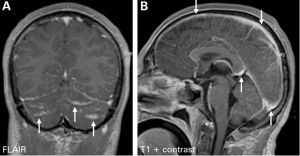

本型較少見。1907年,Lacount首先報告,它是新生隱球菌侵犯腦實質後形成的一種炎症性肉芽腫病變,稱為隱球菌性腦肉芽腫,常好發於大腦、小腦、腦幹的延髓部位。臨床症狀與體徵隨肉芽腫病變的部位和範圍不同以及是否合併腦膜損害而異,位於腦實質內的肉芽腫,其症狀、體徵與腦瘤相似,臨床上難以鑑別,腦脊液壓力常增高,細胞數輕度增多,墨汁塗片及真菌培養可發現隱球菌,但陽性率低。CT、MRI檢查、腦血管造影、腦室造影、腦超聲檢查等,均可能發現腦部占位性病變,術前常難於確診,須行開顱探查術,術中可見肉芽腫表現為魚肉樣腫塊,病理切片發現隱球菌可確診。